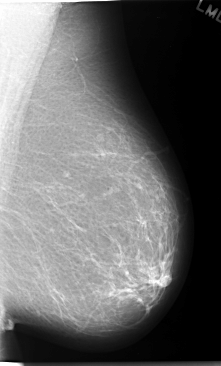

C_0057_1.LEFT_MLO

LEFT_MLO LINES 5848 PIXELS_PER_LINE 3536 BITS_PER_PIXEL 12 RESOLUTION 50 NON_OVERLAY